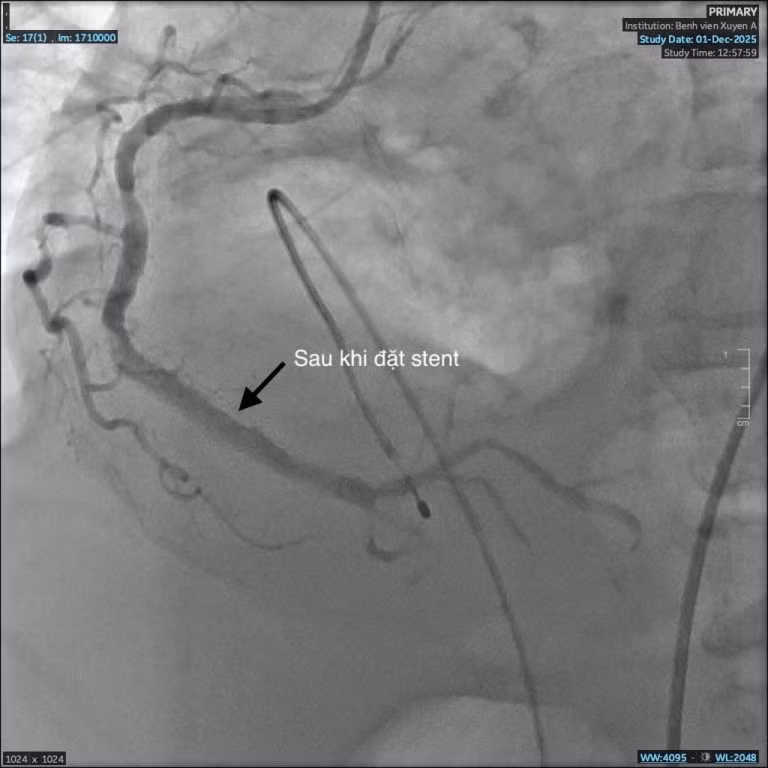

Mạch máu trước can thiệp hẹp đến 95% - Ảnh BVCC

Kết quả chụp động mạch vành phát hiện bà C. bị hẹp nặng ba nhánh mạch vành, rơi vào nguy kịch nhồi máu cơ tim. Đây là nguyên nhân chính khiến bà khó thở, đau nặng ngực.

Với bệnh lý nhồi máu cơ tim nguy hiểm này, nếu không được phát hiện và can thiệp kịp thời, người bệnh sẽ rơi vào nguy cơ sốc tim, rối loạn nhịp dẫn đến tử vong. Không chần chừ, các bác sĩ khoa Can thiệp Tim mạch quyết định can thiệp nong và đặt stent động mạch vành nhằm tái thông dòng máu nuôi tim.

Trong quá trình can thiệp, dưới hướng dẫn của hệ thống số hóa xóa nền DSA, ê-kíp nhận thấy mạch vành của bệnh nhân bị vôi hóa nhiều do đái tháo đường, suy thận lâu năm.

Vôi hóa là “kẻ thù” của can thiệp mạch vành, gây khó khăn cho việc nong và đặt stent, thậm chí khiến việc can thiệp thất bại. Nhưng với sự tỉ mỉ và kinh nghiệm xử trí nhiều ca đặt stent phức tạp trước đó, các bác sĩ khoa Can Thiệp Tim Mạch đã vượt qua thách thức và đặt stent thành công, tái thông mạch máu nuôi tim, cứu bà C. qua cơn nguy kịch”.